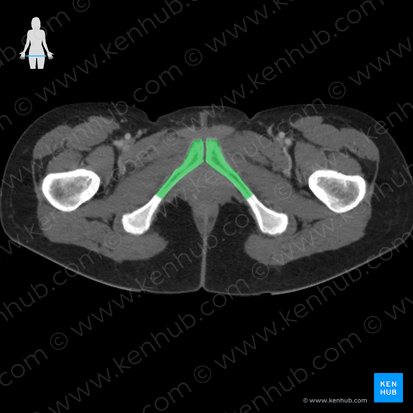

Le pubis se compose d'un corps et de deux branches (supérieure et inférieure). Sur la face antérieure du corps du pubis se trouve un épaississement osseux appelé crête pubienne. La face latérale de cette crête est marquée par le tubercule pubien. Les deux branches du pubis se rejoignent médialement au niveau du corps du pubis. Latéralement, la branche pubienne inférieure rejoint l'ischion, tandis que la branche pubienne supérieure rejoint l'ilion. Ensemble, l'ilion, l'ischion et la branche supérieure du pubis forment l'acétabulum, communément appelé la cavité de l'articulation coxofémorale. Le canal obturateur se trouve entre les branches supérieure et inférieure du pubis. Les deux os du pubis s'articulent sur la ligne médiane au niveau de la symphyse pubienne.

Parties | Corps du pubis Branche supérieure du pubis Branche inférieure du pubis Crête du pubis Tubercule pubien Pecten du pubis / Ligne pectinéale du pubis Surface symphysaire du pubis |